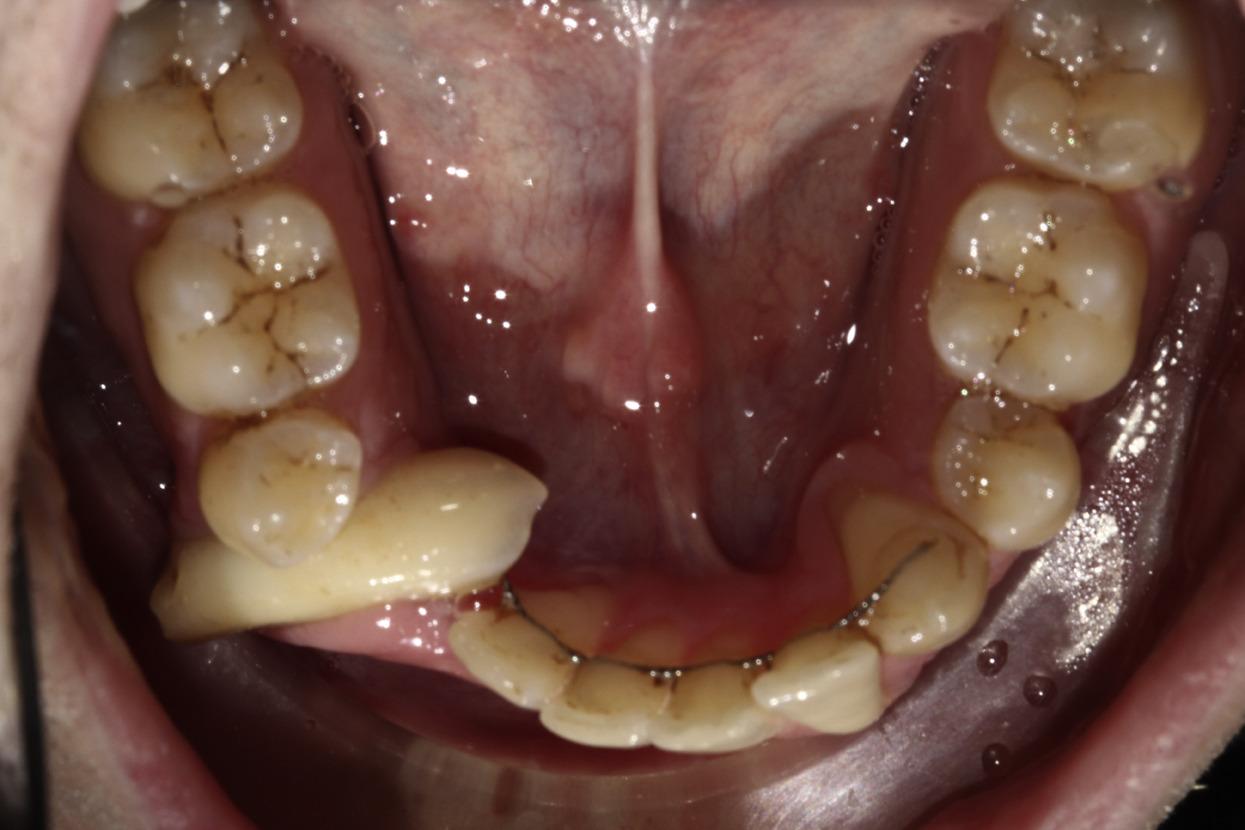

Diş əti (gingiva)